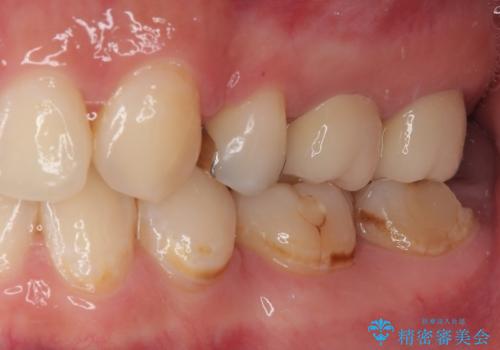

機能面、見た目ともに大変喜んでいただきました。

来院回数を少なくしたいとのご希望もあり親知らず抜歯と同日に仮歯に変えています。

歯茎の治癒を待つ間に痛み等ないことを確認できたので最終的な型どりを行いました。

今後は定期的にメンテナンスに通っていただく予定です。